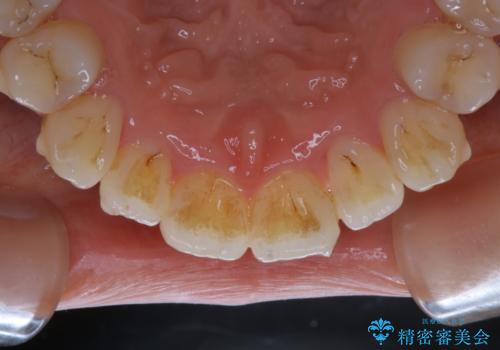

- インビザラインでの矯正治療中ですが、結婚式があるため全体の着色・ステインを綺麗にしたいとのことでした。PMTC60分コースを行いました。

PMTC(保険外治療)は、毎日の歯磨きで落としきれない汚れや、コーヒ、紅茶・タバコのヤニなどの着色も除去します。目には見えない歯と歯の間・歯肉の境目・インビザライン中はアタッチメント周囲などに残っているプラーク(歯垢)もしっかり取り除きます。PMTCでは専門的な機械や材料を使用して、徹底的に汚れを除去するため、虫歯・歯周病・口臭予防などにつながります。

またPMTCを行うことで、ご自身本来の歯の色になり自然な明るさになります。